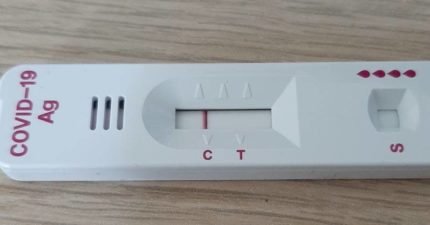

「從未確診」是天選之人?研究曝悲劇真相:比一般人糟糕